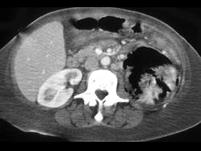

问题 女,63岁,高热、左侧腰痛伴尿频、尿痛,请根据所示图像,选择最可能诊断 ( )

选项 A、慢性肾盂肾炎 B、黄色肉芽肿性肾盂肾炎 C、化脓性肾盂肾炎 D、气肿性肾盂肾炎 E、左肾脓肿

答案 D